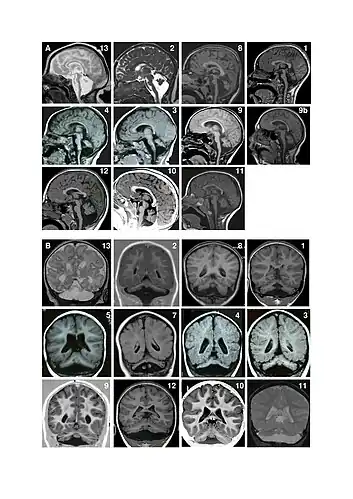

Pontocerebellar hypoplasia (PCH) is a heterogeneous group of rare neurodegenerative disorders caused by genetic mutations and characterised by progressive atrophy of various parts of the brain such as the cerebellum or brainstem (particularly the pons).[1]

There are different signs and symptoms for different forms of pontocerebellar hypoplasia, at least six of which have been described by researchers. All forms involve abnormal development of the brain, leading to slow development, movement problems, and intellectual impairment.[2]